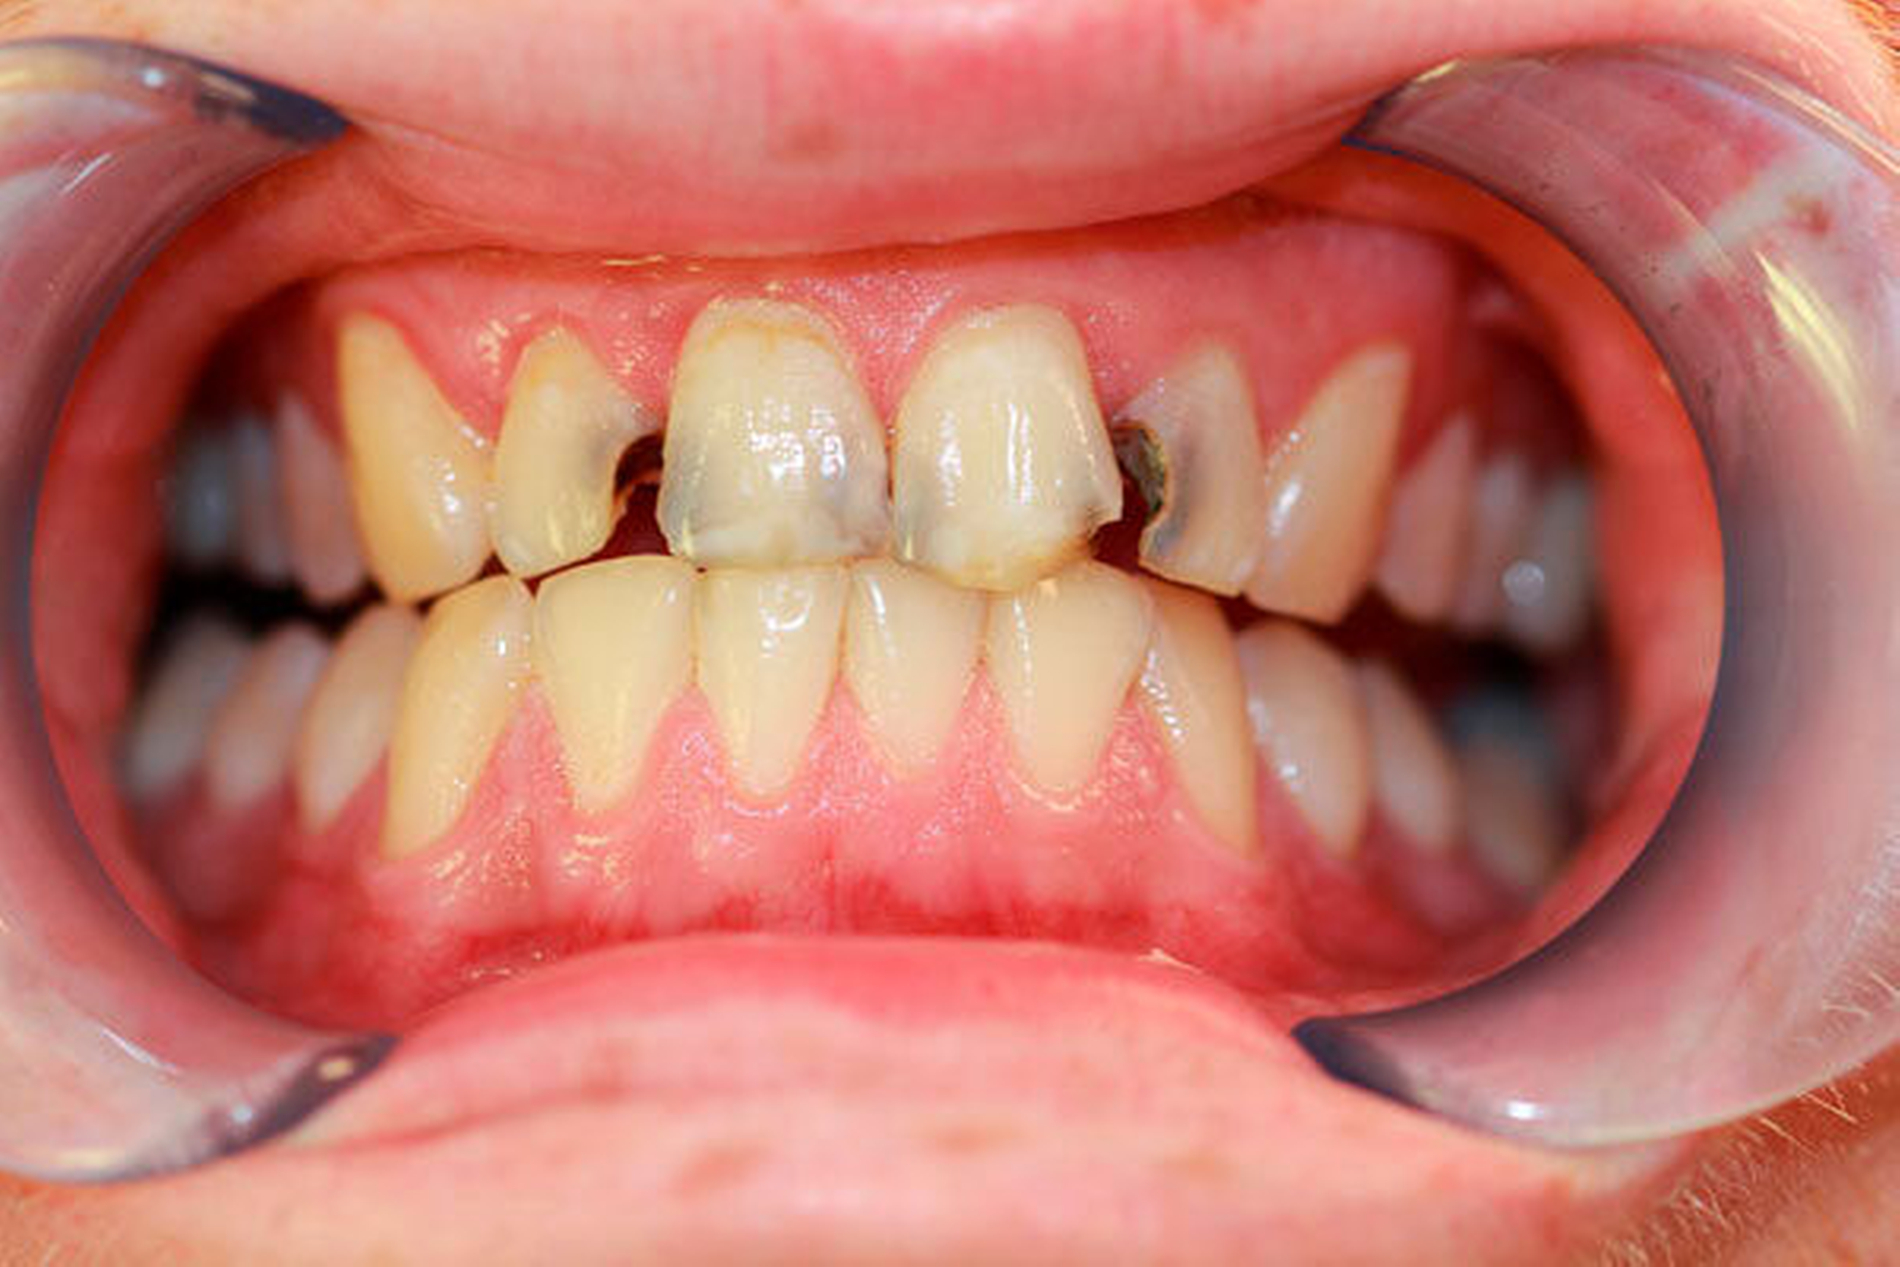

Bei chronischem Crystal-Meth(CM)-Konsum wurde eine Vielzahl körperlicher und psychischer Langzeitwirkungen, beispielsweise Herz-Kreislauf-Erkrankungen, strukturelle Hirnschädigungen und Persönlichkeitsveränderungen, beobachtet [Hamamoto et al., 2009]. In der aktuellen Literatur werden außerdem schwerwiegende Auswirkungen auf die Zahn-, Mund- und Kieferregion beschrieben [Hamamoto et al., 2009; Rhodus et al., 2008]. In den USA, wo nach Schätzungen knapp ein Drittel der weltweit über 30 Millionen CM-Abhängigen lebt, wurde 2005 erstmals der Begriff des „Meth mouth“ in der Fachliteratur genannt [Hamamoto et al., 2009; Rhodus et al., 2005] (Abbildung 1). Dabei wurden fünf Kardinalsymptome beschrieben: 1. Grassierende Karies (Abbildungen 2 und 3), 2. Gingivitis und Parodontitis, 3. Xerostomie, 4. Bruximus und 5. Trismus [Hamamoto et al., 2009; Rhodus et al., 2008].